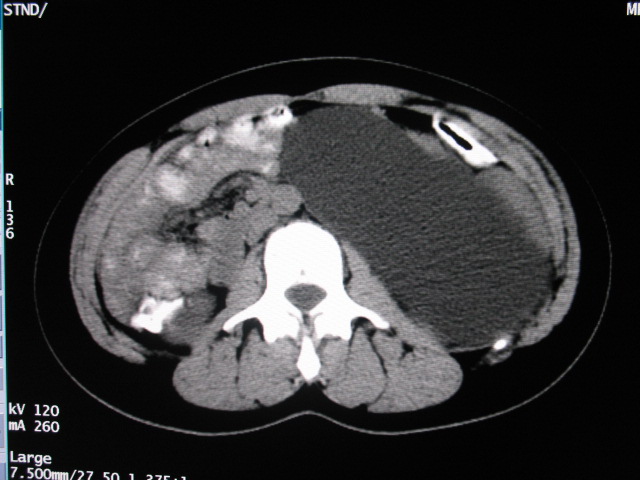

女,28岁,自觉腹部包块一年余

考虑左侧双肾盂双输尿管畸形,其中一输尿管末端梗阻(不排除异位开口可能)并相应之肾盂及输尿管明显扩张积水。

支持;左侧双肾盂双输尿管畸形,其中一输尿管末端梗阻并输尿管肠管样扩张迂曲、肾盂囊状扩张积水。

左双肾盂输尿管畸形.其一输尿管远端输尿管囊肿引起一肾盂输尿管积水.

术后证实是左侧双肾盂双输尿管畸形,巨输尿管巨肾盂症